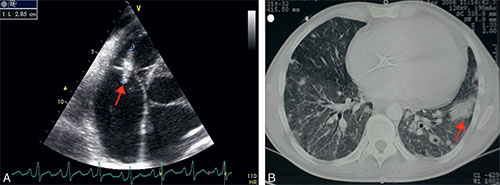

• On note des signes respiratoires liés à des pneumopathies infectieuses récidivantes et souvent abcédées, secondaires aux embolies pulmonaires septiques provenant des végétations du cœur droit (cf. fig. 9.6, vidéo 9.5 et vidéo 9.6).

Fig. 9.6

Échographie transœsophagienne (A) montrant une végétation (flèche) sur la valve tricuspide d’un patient toxicomane IV et scanner pulmonaire (B) montrant une pneumopathie bilatérale avec abcès pulmonaire (flèche) liée à des embolies pulmonaires septiques chez le même patient.